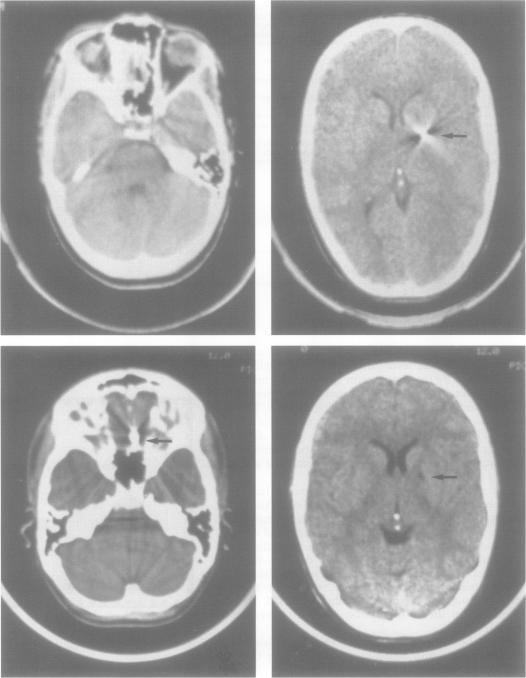

Spontaneous migration of airgun pellet in the brain.

J Neurol Neurosurg Psychiatry. 1994 Apr;57(4):404. doi: 10.1136/jnnp.57.4.404.